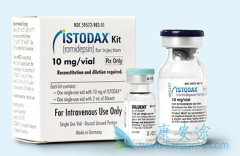

治愈HIV需要从全身免疫细胞中的贮库中根除潜伏的病毒。HIV潜伏期取决于人类宿主蛋白质的活性,称为组蛋白去乙酰化酶(HDAC),之前的研究表明,HDAC抑制剂(HDACi)可以破坏HIV潜伏期。丹麦OleSgaard及其同事研究了 罗米地辛 (Romidepsin)的临床安全性 ...

在临床上炎症性乳腺癌十分难治,是局部晚期乳腺癌最具转移性的变异。不过据Kimmel癌症中心研究人员称, 罗米地辛 (Istodax)在炎症性乳腺癌的临床前研究中显示出惊人的益处。Kimmel癌症中心开展了1/2期临床试验,以测试罗米地辛(Istodax-)与nab-紫杉 ...

SHANK3基因的单倍体不足与自闭症谱系障碍(ASD)有因果关系,并且ASD相关基因也富集染色质重塑。研究针对因Shank 3基因缺陷而患有自闭症的实验鼠,用低剂量 罗米地辛 进行为期3天的治疗,发现改善社交行为的效果能持续约3周,相当于人类的几年。罗地米辛 ...